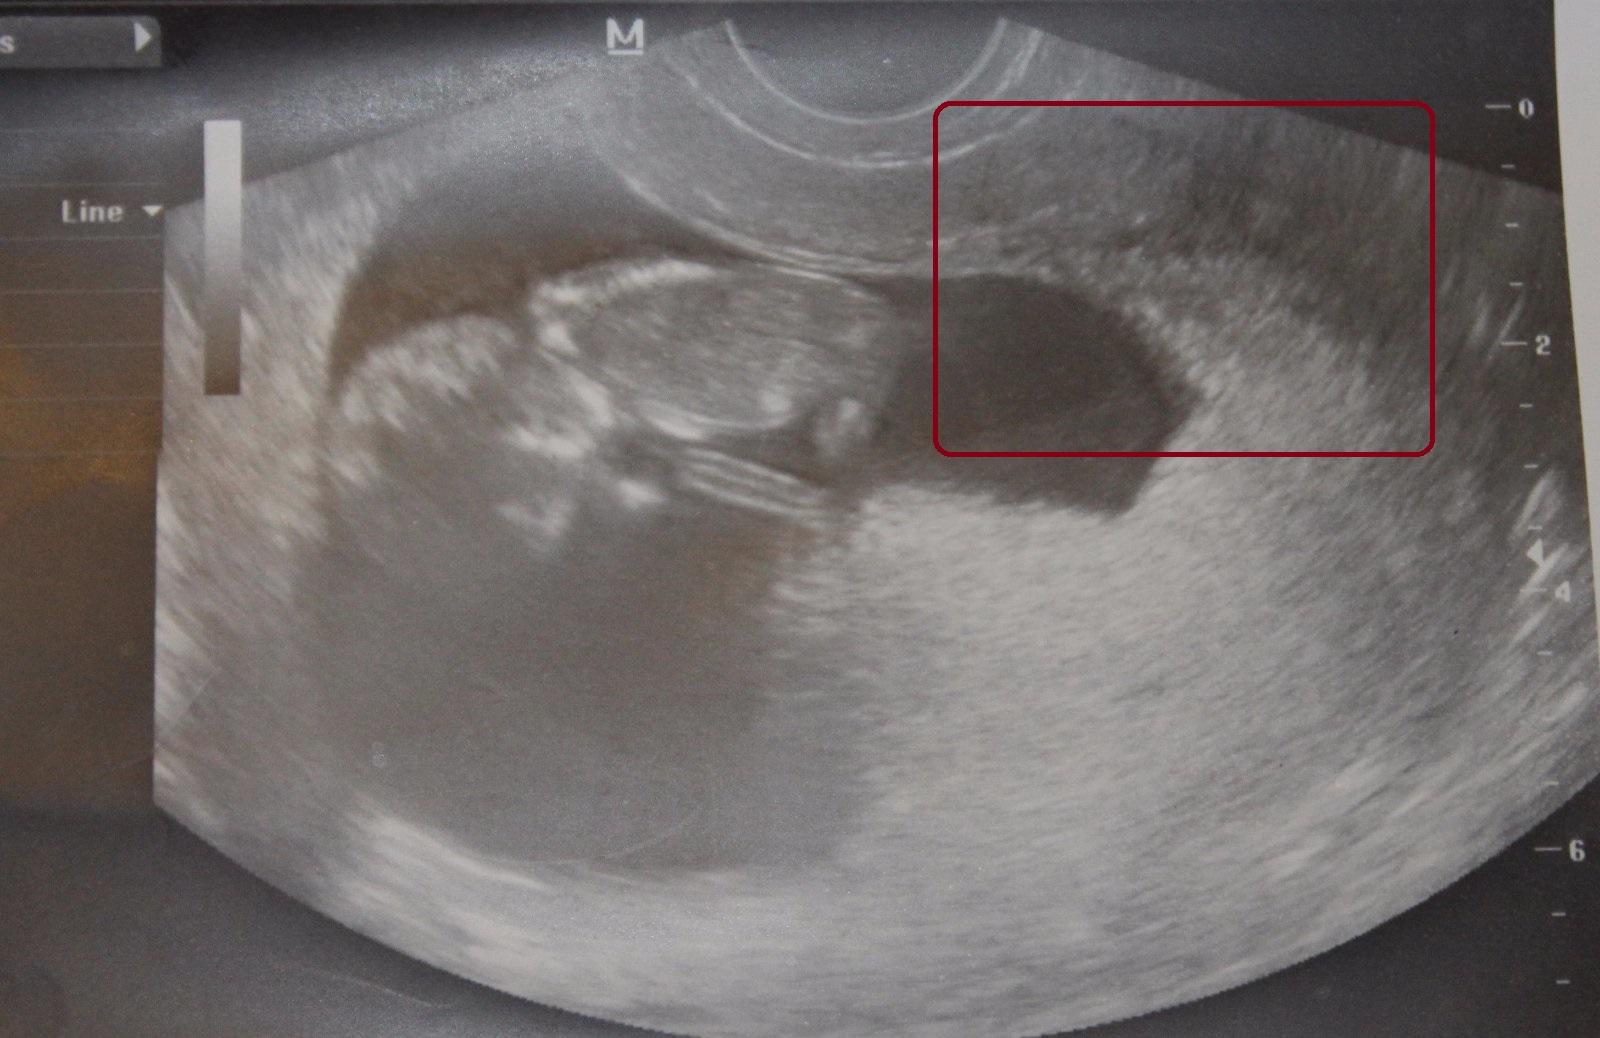

Ahojte maminy a cakatelky, prosim vas pekne, zda sa to iba mne alebo vidite na obrazku z UZ viac ako jedno babatko? dve fotky vytvorene tesne po sebe a na prvej vidim vpravo v hornom rohu (akoby za ciernou dutinou) babatko spredu (hlavicka a lava rucicka) a hned na druhej zozadu akoby stavce, hlavicku a svetle "ciarky" - nozicky. Totiz cim viac to pozorujem, tym viac neviem na com som. Podla mna sa pocas "fotenia" otocilo lebo aj to prve sa velmi rychlo stale hybalo. Prosim vidi este niekto okrem mna viac ako jedno dietatko ci nie? dakujem za vase nazory, DAKUJEM velmi velmi!

PS to dietatko ( aj ked vidno iba jeho cast) v strede v tej tmavociernej casti je iste a potvrdene doktorom... ;)

no niektore tu sklamem, pri jednovajecnych 2jkach vobec nesu 2 plodove vaky, ja som mala krasny jeden plodovy v cca6tt a krasne jedno za druhy sedelo, len zial u nas to nevyslo a vyvrcholil to syndrom vstrebaveho 2jcata na dalsom UZ bolo iba jedno.. tu autorka @stratenanajdena ak ma zrak neklame, su 2 tiez za sebou ale obratene cize jedno je hlavickou pri nozkach toho co je kresne vidiet, drzim palce a zdrave tehulkovanie 😉